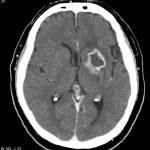

COVID-19-Impfung: Gehirnblutung mit Ventrikelriss: Noch einer dieser Einzelfälle nach Gentherapie mit Pfizers Comirnaty

Die Frage, wann die Nebenwirkungen nach Impfung so zahlreich sind, dass man sie a) nicht mehr unter den Teppich kehren und b) als Einzelfall abtun kann, wie das derzeit getan wird, in einem Experiment in Kollektivismus, das man auf die Formel bringen […]